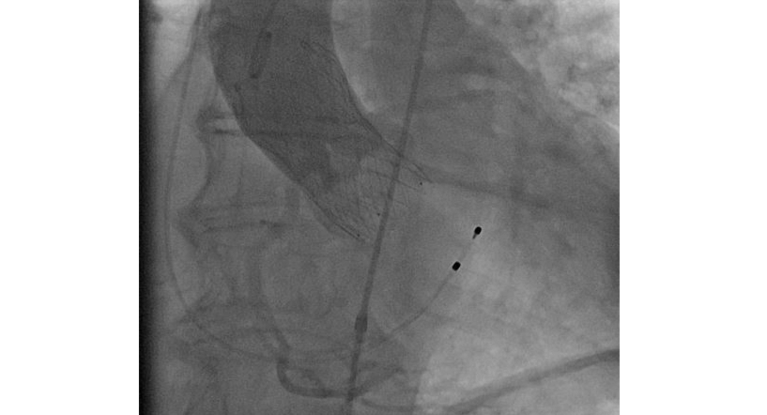

Angiographie: neue TAVI-Prothese, Medtronic Evolut FX

Angiographie: neue TAVI-Prothese, Medtronic Evolut FX.

Das neue TAVI-System wurde grundlegend optimiert und mit neuen Eigenschaften ausgestattet. Die wesentliche Verbesserung sind integrierte Röntgenmarker, die den behandelnden Ärzt*innen als präzise Orientierungspunkte dienen, um die Aortenklappe optimal zu platzieren und auszurichten. Zusätzlich wurde das Einführungs- und Freisetzungssystem der Herzklappe für eine maximale Präzision weiterentwickelt. Die verbesserte Stabilitätsschicht gewährleistet eine erhöhte Unterstützung und Kontrolle des Katheters während des Eingriffs. Der Bewegungsspielraum wurde erweitert und das System passt sich jetzt flexibel der individuellen Anatomie der Patient*innen an.